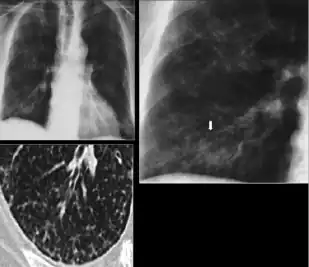

3. Nodule with poorly defined margins - Round density within the lung parenchyma, also called a tuberculoma. Nodules included in this category are those with margins that are indistinct or poorly defined (tree-in-bud sign[3]). The surrounding haziness can be either subtle or readily apparent and suggests coexisting airspace consolidation.

-

Chest x-ray showing nodule with margins that are indistinct or poorly defined (tree-in-bud sign) in post-primary pulmonary TB.